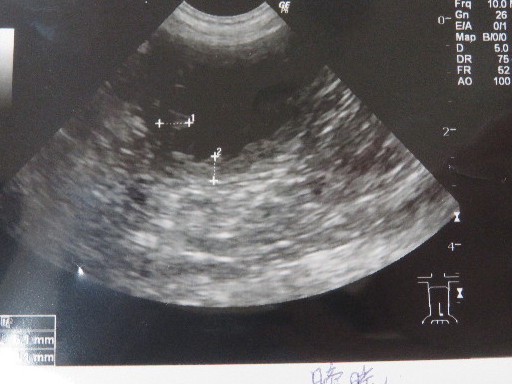

○胆泥はあいかわらずです。

下に濃く溜まっているのと、浮遊しているものと両方。